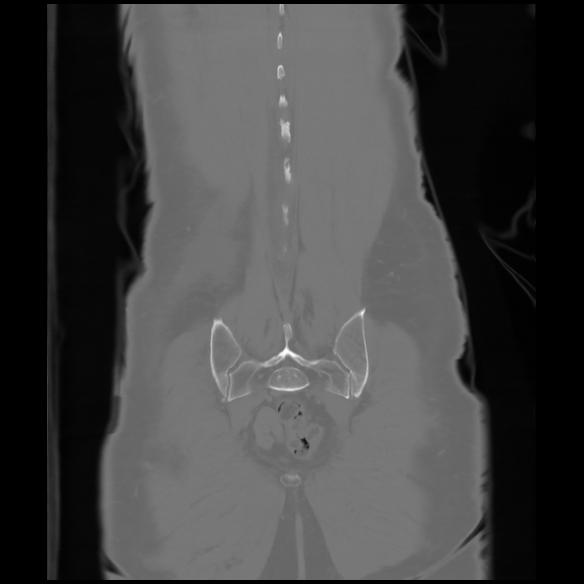

6 CUERPO,CE,Coronal,3.000,CUERPO,Coronal,